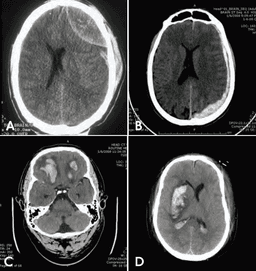

Вогнищеві ураження включають епідуральні гематоми, субдуральні гематоми, забої та внутрішньомозкові гематоми (рис. 6–7).

Рис. 6–7. КТ внутрішньочерепних гематом.

А. Епідуральна гематома.

В Субдуральна гематома.

С. Двосторонні забої з крововиливами.

D. Інтрапаренхімальний крововилив справа із зсувом серединної лінії справа наліво та вторинні бівентрикулярні крововиливи.

Важливими результатами КТ голови є набряк шкіри або підапоневротична гематома в області травми. Переломи черепа можна діагностувати, застосувавши на КТ режим найкращої візуалізації (bone window), хоча їх видно навіть у режимі для м’яких тканин. Важливими результатами на КТ голови є також внутрішньочерепна гематома, забої, зрушення серединної лінії (ефект новоутворення) та облітерація базальних цистерн (Див. рис. 6–7). Зміщення на 5 мм або більше часто свідчить про необхідність хірургічного видалення тромбу або забою, що викликає зміщення.